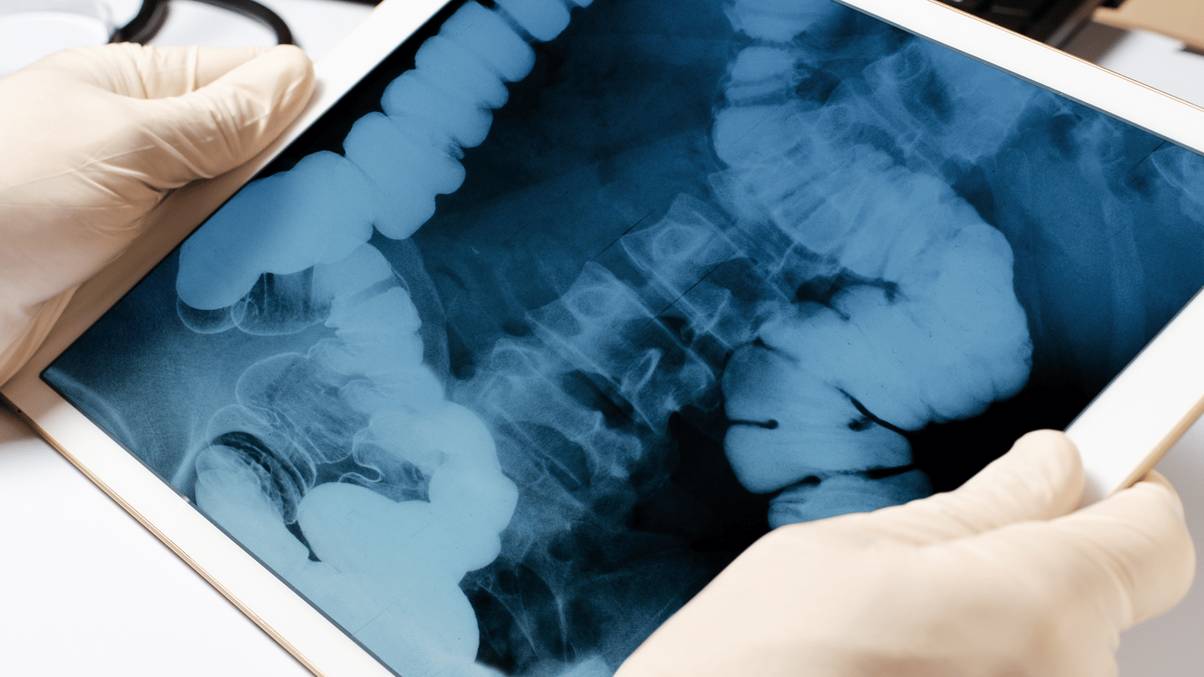

The military-grade projectile which dates again to 1918, reportedly measuring 16cm in size and 4cm in diameter, was jammed up his rectum.

After surprised surgeons on the Rangueil Hospital in Toulouse, France, discovered the item wedged up there, they realised it hadn’t been detonated – prompting a mass evacuation.

He ended up being whisked to a surgical suite so medics may perform additional investigations, which is when the WW1 relic was discovered inside his anus.